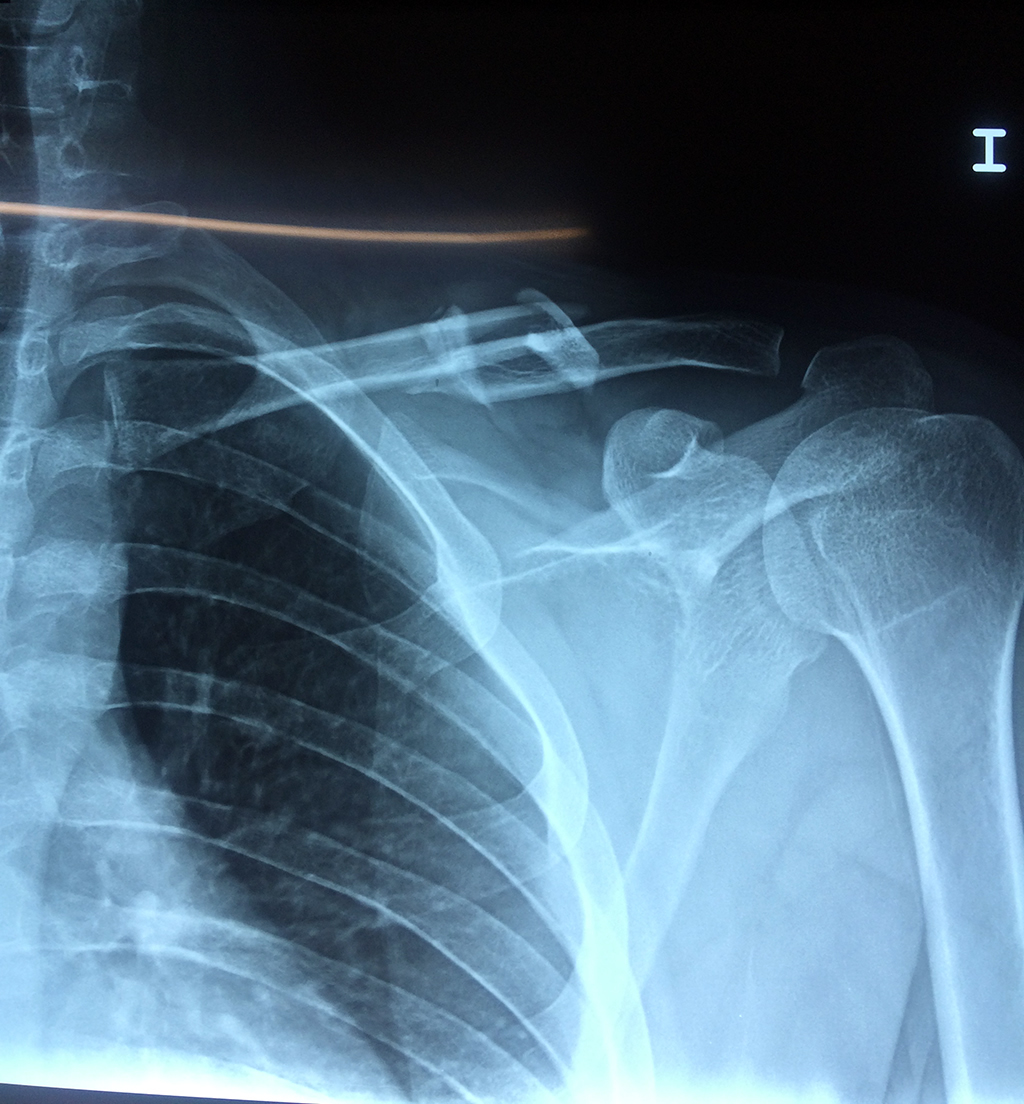

Húmero - Clavícula

La clavícula es un hueso largo, con forma de "S" itálica, situado en la parte anterosuperior del tórax. Junto con la escápula forman la cintura escapular. Se puede palpar por toda su longitud y se extiende del esternón al acromion de la escápula, siguiendo una dirección oblicua lateral y posterior.